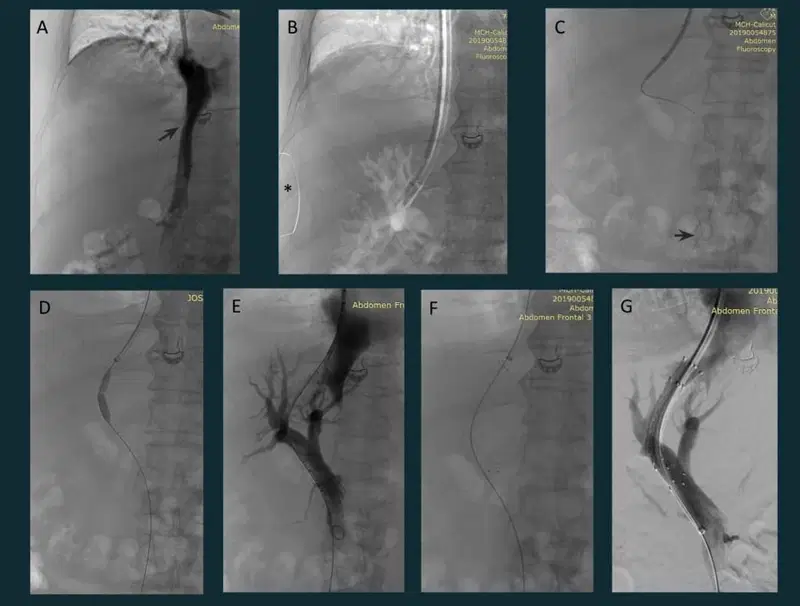

4. TACE (Transarterial Chemoembolization)

Transarterial Chemoembolization

Fifty-four-year-old lady with non-cirrhotic liver and HCC. Treated with transarterial chemoembolization (TACE). A. CECT of the abdomen – arterial phase enhancing lesion in segment VII of the liver. B. Selective celiac artery cannulation with a 4F Simmons diagnostic catheter which was advanced to the common hepatic artery (blue arrow) and a microcatheter (red arrow) was coaxially placed with the tip in the RHA. Superselective cannulation and angiogram of the feeder artery, a branch of right hepatic artery showing tumor blush (*) along with normal parenchymal branches (black arrow). C. Further advancement of the microcatheter (red arrow) to surpass the normal parenchymal branches and chemoembolization (Lipiodol and Doxorubicin emulsion in 2:1 ratio) in process. Lipiodol accumulation in the tumor stroma (*).  After chemoembolization, gel foam embolization of the feeder artery was done. Post embolization angiogram showed complete occlusion of the tumor artery with patent normal parenchymal branches (arrow). Good lipiodol โ€“doxorubicin emulsion deposit is also seen (*).

4a.TACE (contd)

Post Transarterial Chemoembolisation TACE for liver tumors HCC

TACE pre and one-month post-procedure image series show the segment VII lesion (*) with good lipiodol uptake (Type I pattern) in the tumour with no evidence of residual enhancing areas or non-target embolization.